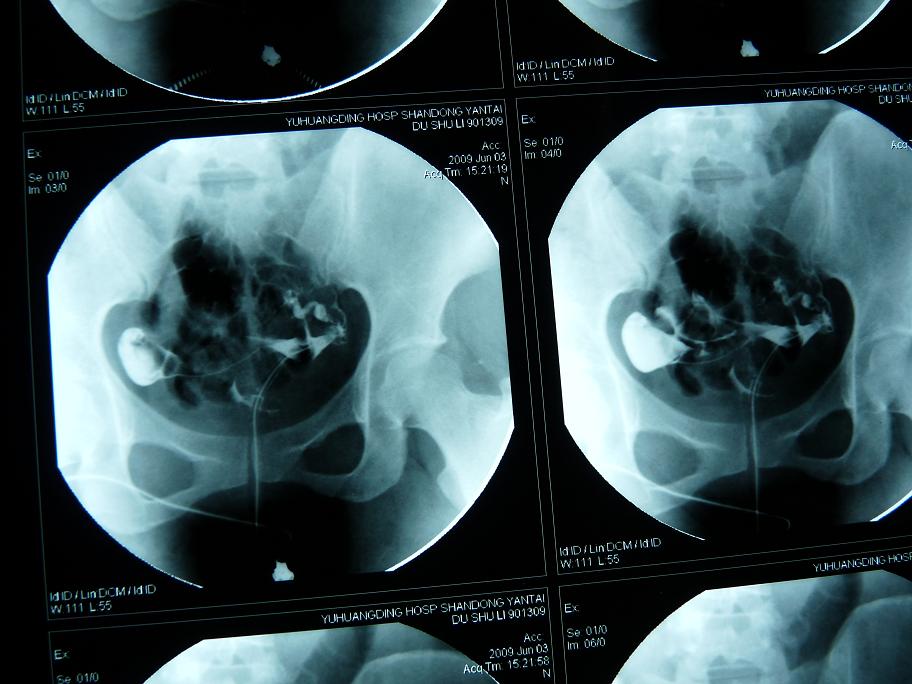

以下是引用黑白光影在2009-6-6 9:58:00的发言:[br]左侧输卵管粗细不均、僵硬、通而不畅,右侧输卵积水。